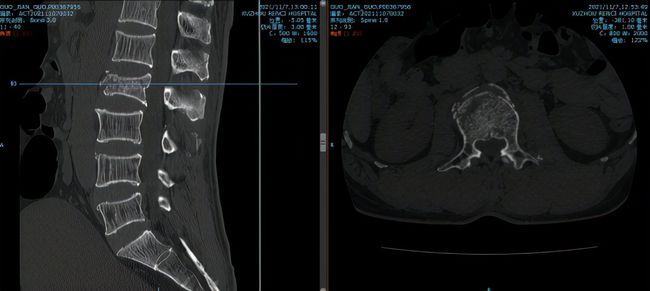

11月初山东的郭大叔如往常一样在厂里干活,突然设备掉落砸伤了其腰背部,当时他就不能动了,家人、同事连忙将他送到当地医院检查,结果ct显示大叔的L2椎体骨折。这可急坏了大叔的家人,家人找亲朋好友四处打听,得知徐州仁慈医院可以做脊柱微创手术,连夜带着郭大叔来我院就诊。

到医院的时候大叔已经背疼了20个小时不得动弹,急诊医务人员赶忙把大叔推到脊柱科检查治疗。脊柱科孟磊副主任医师为大叔检查后,发现他不单单是腰椎骨折,还有胸骨体骨折、腰椎横突骨折、棘突骨折、右侧第3-5、8肋骨骨折伴有肺部挫伤以及胸腔积液。

最终,孟磊副主任医师团队在天玑骨科机器人定位下,通过3D图像扫描规划手术中椎弓根螺钉的进钉点、置钉方向以及置钉深度。根据机器人系统导航,通过机械臂精准定位置钉位置,医生只在置钉部位切开约2cm切口,不损伤其它椎关节,保障神经安全和手术的有效性。